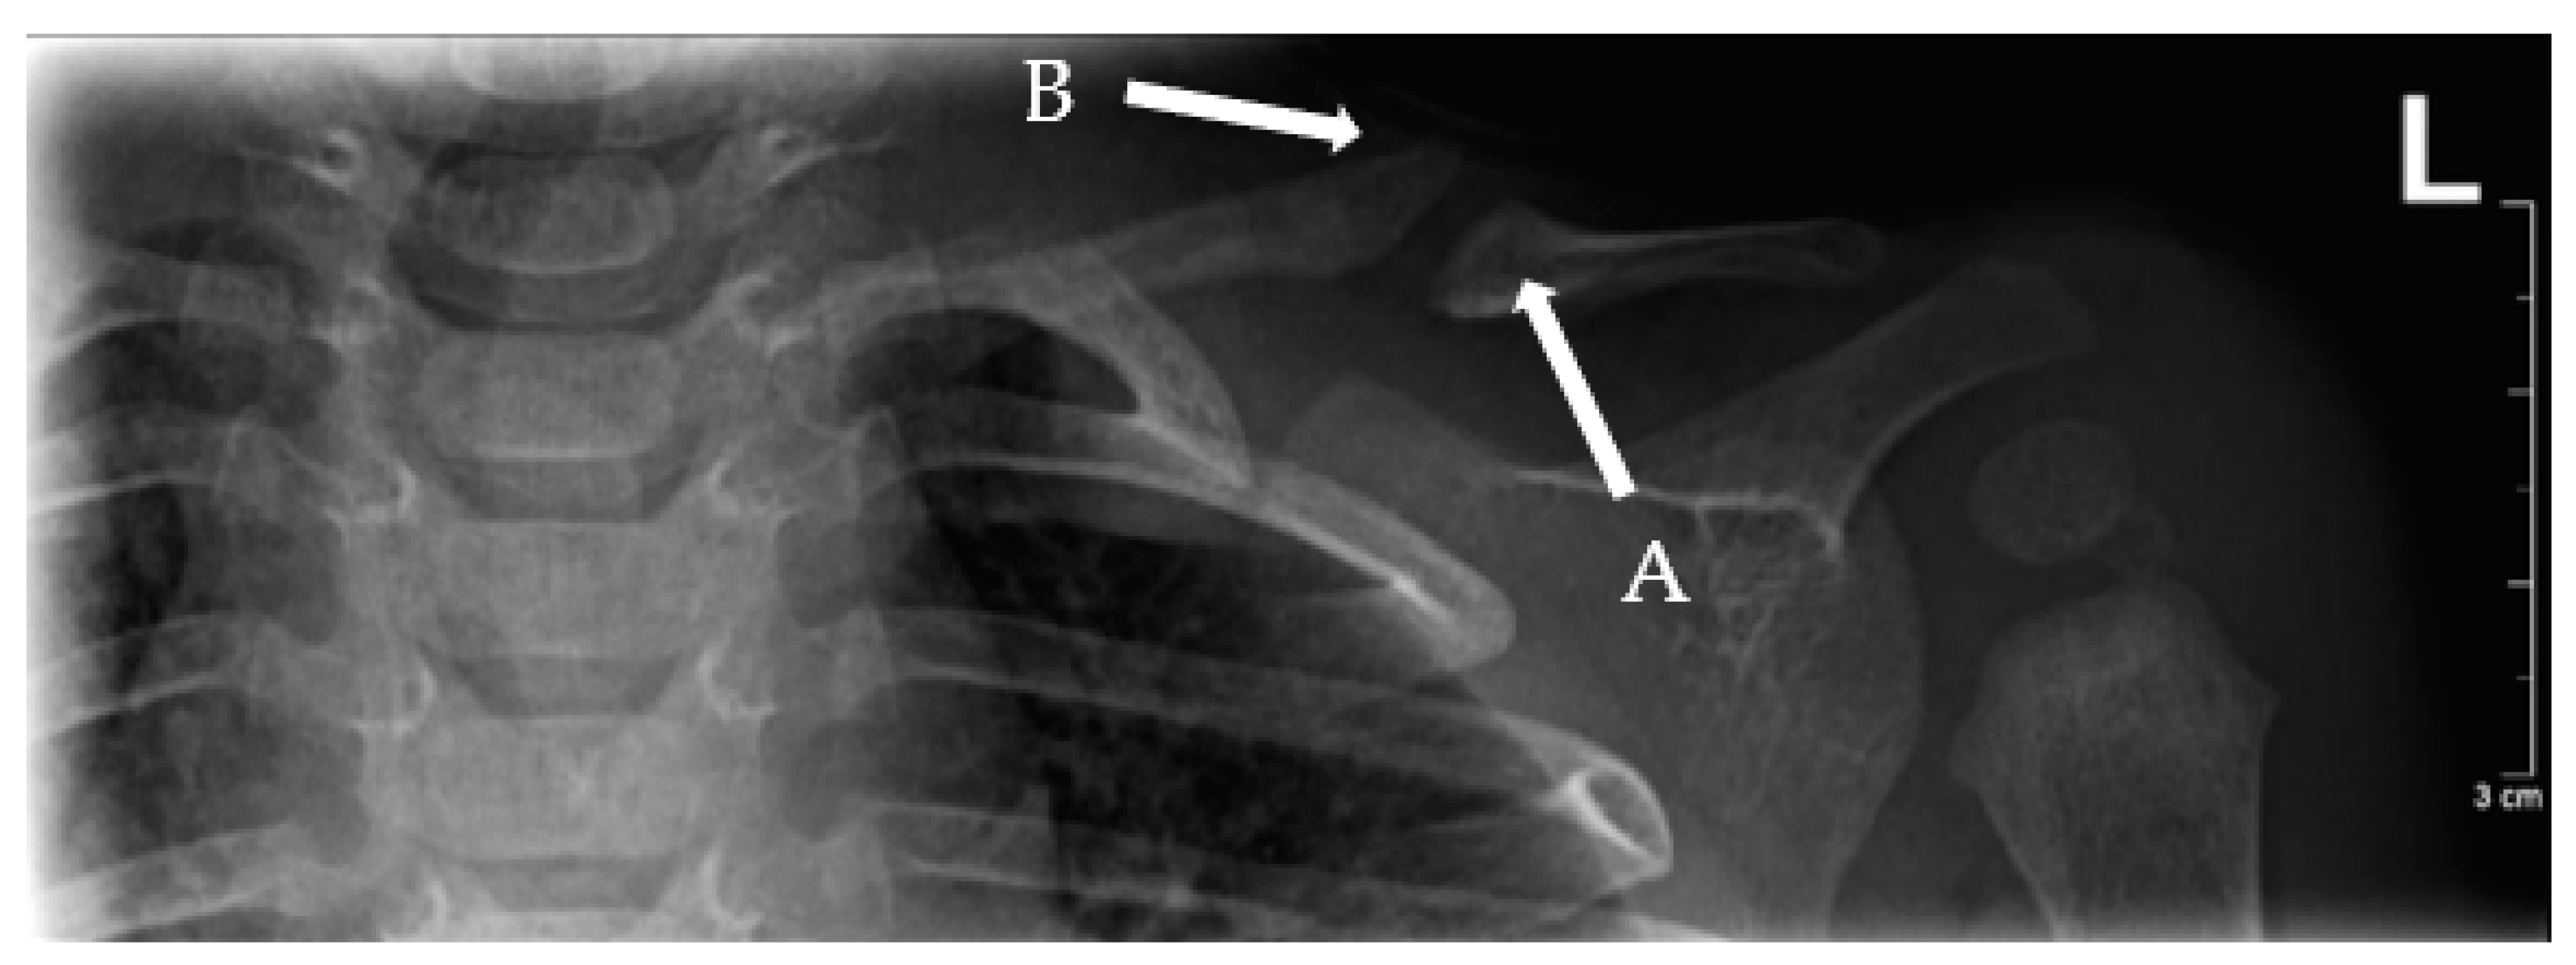

3.2. Pseudarthrosis